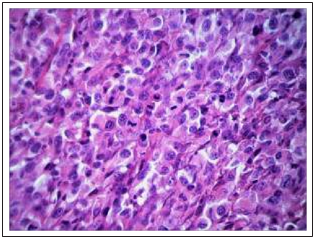

Studies of the morphological features of the DDP-resistant Guerin’s carcinoma architectonics in the rats from control group that were not exposed to Cisplatin-Ebewe® or Feroplat® showed that the major part of the tumors were thecells characterized by moderately pronounced polymorphism with a solid growth pattern. The cells had elongated or rounded form, the cytoplasm with signs of basophilia, large nuclei, some of which were located eccentrically (Fig. 11A). Often there were figures of mitotic division. There were small mosaic patterns of the non-fibrotic and necrotic cells death (Fig. 11B).

Figure 11A: Thesolid character of tumor growth and the tumor cells compact location of DDP- resistant Guerin’s carcinoma (control) (×200)

Figure 11B: Figures of mitoses, including atypical, in tumor cells of DDP-resistant Guerin’s carcinoma (control) (×1000)

Fig.11 Changes in the cytoarchitectonics of DDP-resistant Guerin’s carcinoma under the influence of Cisplatin-Ebewe and Feroplat® (coloring with hematoxylin and eosin).